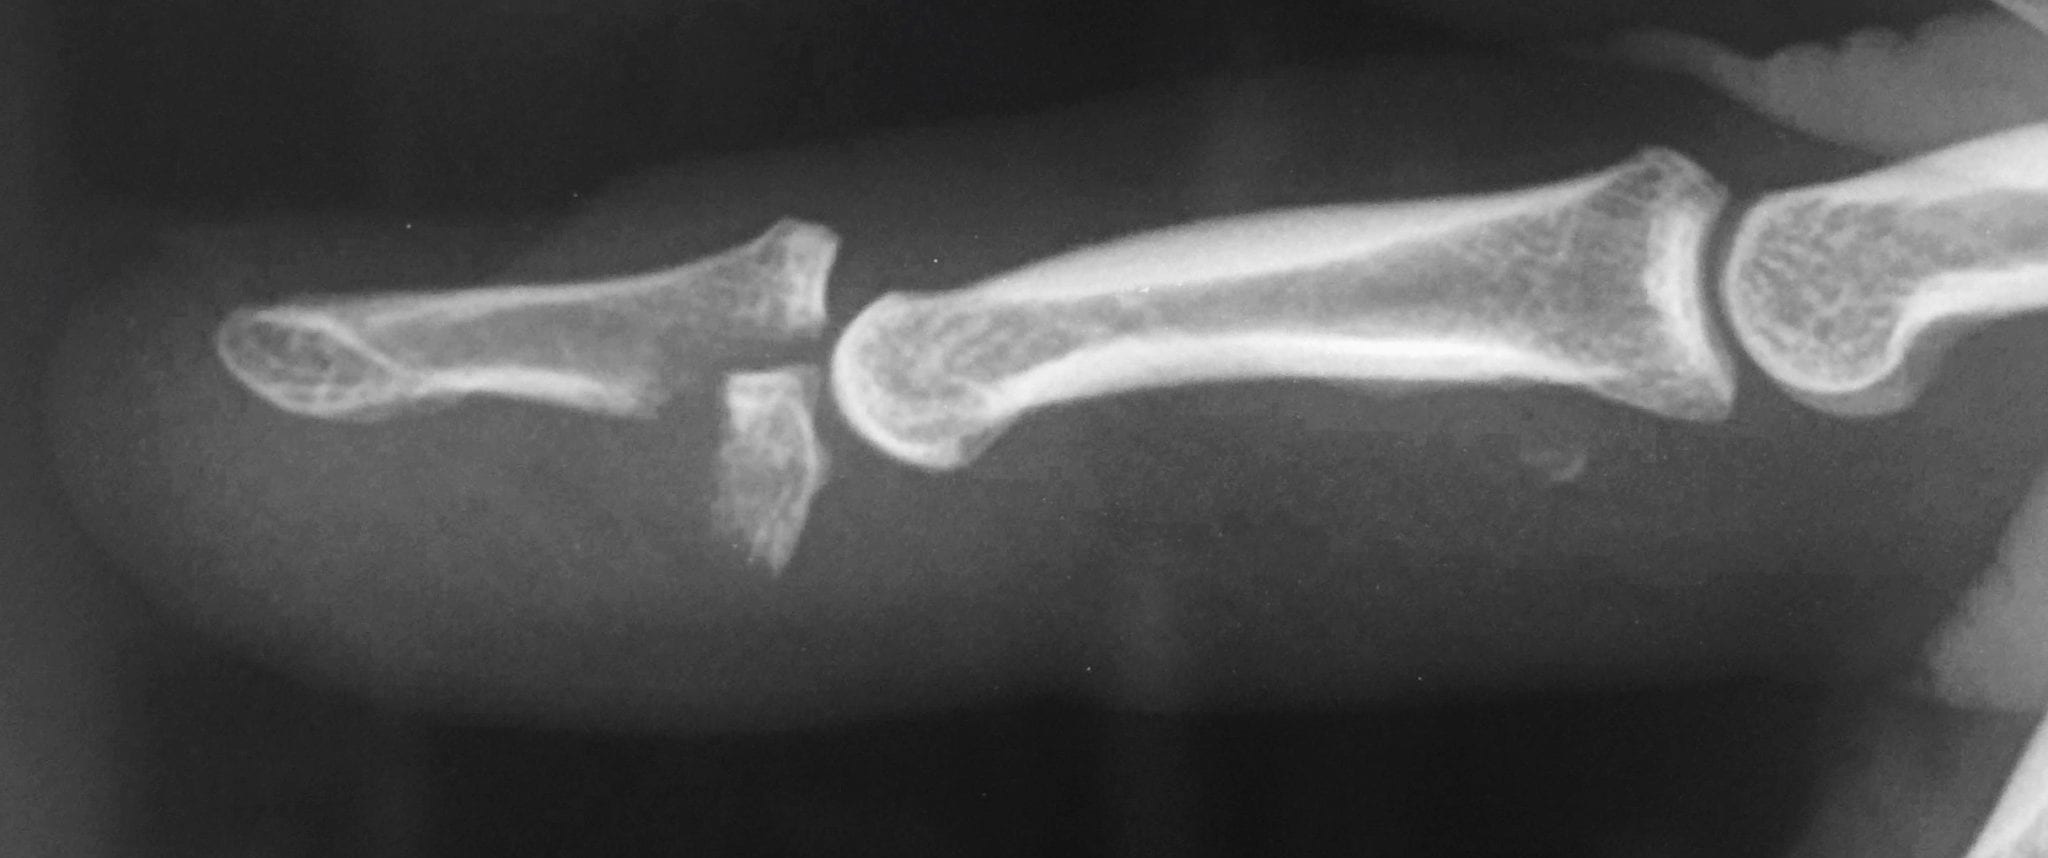

Baseball Finger Radiology . Diagnosis is made clinically when the distal phalanx rests. Mallet finger is a finger deformity caused by disruption of the terminal extensor tendon distal to dip joint. The injury results when an unyielding object (like a ball) strikes the tip of the digit and forces it to bend further than it is intended to go. The injury classically occurs while playing sports where the dip joint undergoes sudden flexion (extended finger is struck at the tip by an. Mallet finger, also known as baseball finger, is an injury to the thin tendon that straightens the end joint of a finger or thumb. Discontinuities of the extensor insertion are often referred to as “mallet injury” or “baseball finger.” they can be purely tendinous or bony avulsion fractures. Mri is an accurate method for. Mallet finger (baseball finger) often caused by a direct blow to the extended digit—there is an avulsion of the extensor.